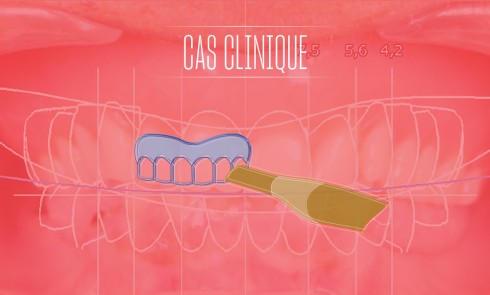

L’arcade s’en trouve très perturbée ; le plan d’occlusion inadapté : sa hauteur, son orientation, une asymétrie (3) Les courbes de compensation sont rarement satisfaisantes pour l’établissement du concept occlusal choisi.

Enfin, une difficulté supplémentaire d’ordre esthétique est omniprésente : il faut obtenir une concordance de dimension, de forme, couleur, d’éventuelles caractérisations.